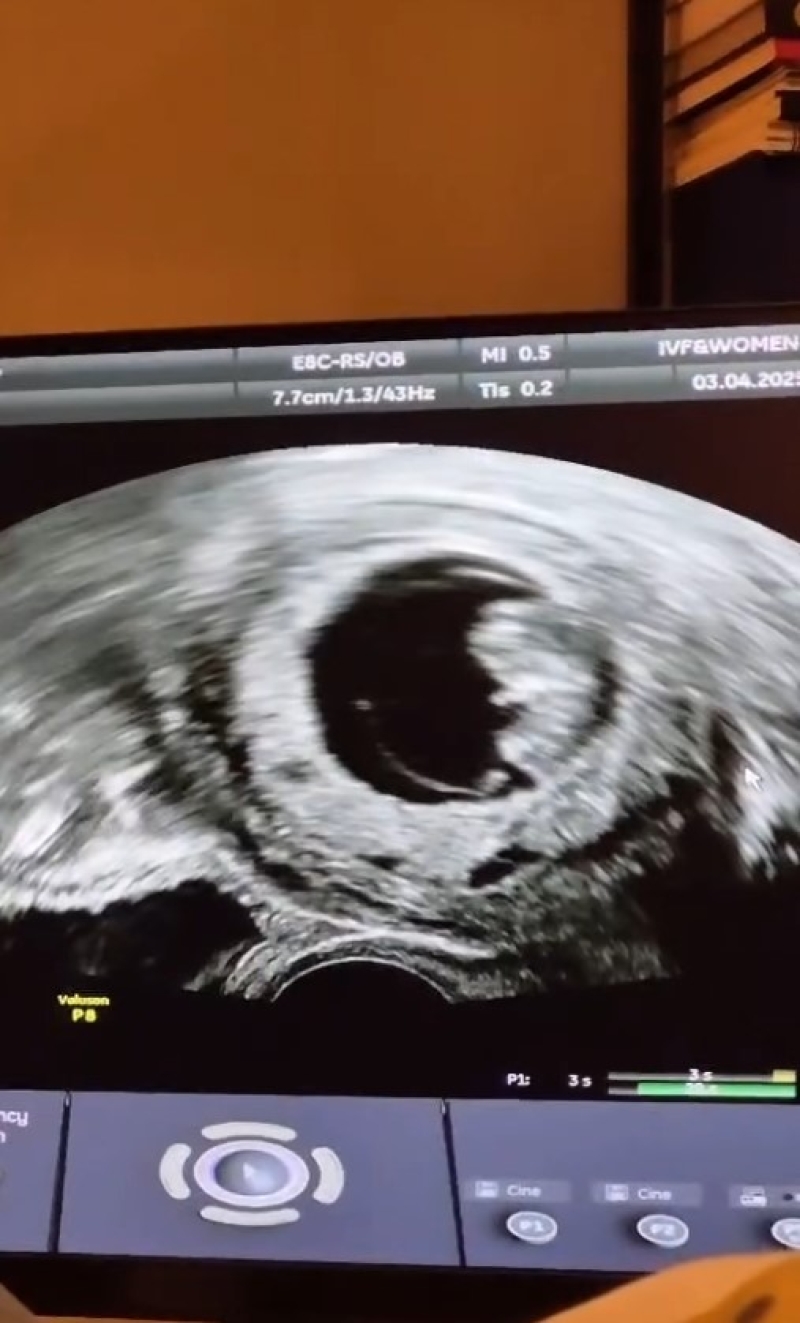

โดยในครั้งนี้ ด้านสาวมน ได้ออกมาเผยควาในใจว่า เธออยากสร้างครอบครัวที่สมบูรณ์และมีลูกมานานแล้ว แต่เนื่องจากเธออยู่ในภาวะมีบุตรยาก เธอจึงพยายามเข้ารับการรักษามาตลอดระยะเวลา 2 ปี ซึ่งเธอและสามีก็ไม่เคยย่อท้อแต่อย่างใด จนในที่สุดวันนี้ก็ประสบความสำเร็จ โดยสาวมน ได้โพสต์แจ้งข่าวดี พร้อมโพสต์รูปภาพอัลตราซาว กล่าวขอบคุณ ทั้งทีมแพทย์ ครอบครัวและเพื่อนๆ ที่คอยให้กำลังใจเสมอมา ท่ามกลางศิลปินและเหล่าแฟนเพลงต่างเข้ากันมาร่วมยินดีให้กับสาวมนกันยกใหญ่กันเลยทีเดียว